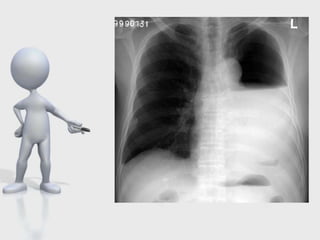

Complicaciónes postneumonectomía

SD. Postneumonectomia